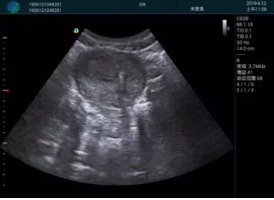

病例一:

清晰顯示孕囊,通過軟件包計算孕齡7w+6d

M20實時引導,術中清晰顯示孕囊被破壞和抽吸針的過程,清晰顯示吸引針

抽吸結束后縱切子宮,孕囊已被完全抽吸,未見明顯殘留

橫切子宮,發(fā)現右側宮腔靠近宮角處有少許脫模樣殘留

M20引導下,抽吸針找到右側宮角處再次清掃

二次抽吸后再次進行超聲檢查,宮腔未見殘留,宮腔線清晰顯示